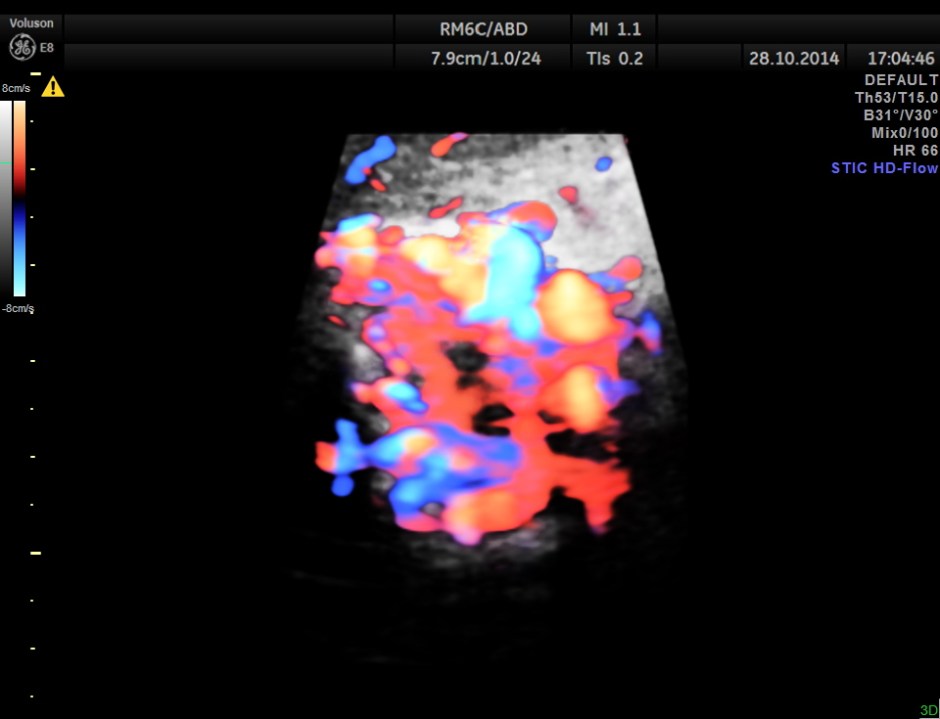

STIC HD flow image.

Main portal vein show flow reversal ( blue colour ) – centri-fugal flow suggestive of portal hypertension.